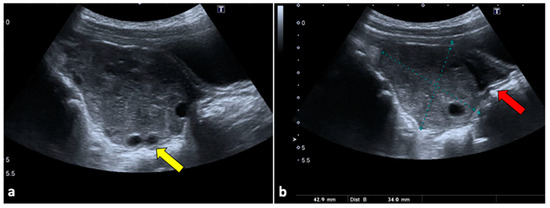

The Diagnostic Accuracy of Magnetic Resonance Imaging for Maternal Acute Adnexal Torsion during Pregnancy: Single-Institution Clinical Performance Review

by Jong Hwa Lee, Hyun Jin Roh, Jun Woo Ahn, Jeong Sook Kim, Jin Young Choi, Soo-Jeong Lee and Sang Hun Lee

J. Clin. Med. 2020, 9(7), 2209; https://doi.org/10.3390/jcm9072209 - 13 Jul 2020

Cited by 15 | Viewed by 6784

Background: For acute adnexal torsion of pregnant women, appropriate treatment based on an accurate diagnosis is especially important for fertility preservation and timely treatment. The 2017 American College of Obstetricians and Gynecologists (ACOG) Committee Opinion No. 723 announced its practice-changing guidelines to ensure [...] Read more.

Background: For acute adnexal torsion of pregnant women, appropriate treatment based on an accurate diagnosis is especially important for fertility preservation and timely treatment. The 2017 American College of Obstetricians and Gynecologists (ACOG) Committee Opinion No. 723 announced its practice-changing guidelines to ensure that diagnostic magnetic resonance imaging (MRI) conducted during the first trimester and gadolinium exposure at any time during pregnancy are safe for fetal stability. Unfortunately, few studies have been performed to evaluate the usefulness of the diagnostic accuracy of MRI for acute adnexal torsion during pregnancy. Objective: We sought to determine the efficacy of diagnostic MRI modality using multiparameter for maternal adnexal torsion during pregnancy. Methods: From 1 January 2007 to 31 January 2019, 131 pregnant with MRI tests were reviewed. In this retrospective cohort study, 94 women were excluded due to conditions other than an adnexal mass, and 37 were identified through MRI analyses conducted before surgery for suspected adnexal torsion. The primary outcome was the diagnostic accuracy of sonography and MRI, and the secondary outcome was the usefulness of Apparent diffusion coefficient (ADC) values for predicting the severity of hemorrhagic infarction between the medulla and cortex of the torsed ovarian parenchyma. Results: Our study demonstrates that in the diagnosis of adnexal torsion during pregnancy, the sensitivity, specificity, positive predictive value, and negative predictive value are 62.5%, 83.3%, 90.9%, and 45.5% for sonography and 100%, 77.8%, 90.5%, and 100% for MRI. MRI results in surgical-proven adnexal torsion patients revealed unilocular ovarian cysts (36.8% (7/19)), multilocular ovarian cysts (31.6% (6/19)), and near normal-appearing ovaries (31.6% (6/19)). Pathology in adnexal torsion revealed a corpus luteal ovarian cyst (63.2% (12/19)) and underlying adnexal pathology (46.8% (7/19)). Maternal adnexal torsion during pregnancy was more likely to occur in corpus luteal ovarian cysts than in underlying adnexal masses (odds ratio, 2.14; 95% confidence interval (CI), 0.428–10.738). MRI features for adnexal torsion were as follows: tubal wall thickness, 100% (19/19); ovarian stromal (medullary) edema, 100% (19/19); symmetrical or asymmetrical ovarian cystic wall, 100%(19/19); prominent follicles in the ovarian parenchyma periphery, 57.9% (11/19); periadenxal fat stranding, 84.2% (16/19); uterine deviation to the twisted side, 21.1% (4/19); and peritoneal fluid, 42.1% (8/19). The signal intensity of the ADC values of the ovarian medulla and cortex were compared between the cystectomy and detorsion (CD) and salpingo-oophorectomy (SO) groups. The ADC values of the CD and SO groups were 1.81 ± 0.09 × 10−3 mm2/s and 1.91 ± 0.18 × 10−3 mm2/s, respectively (P = 0.209), in the ovarian medulla and 1.37 ± 0.32 × 10−3 mm2/s and 0.96 ± 0.36 × 10−3 mm2/s, respectively (P = 0.022), in the ovarian cortex. The optimal cut-off value of ADC values for predictable total necrosis in the torsed ovarian cortex was ≤ 1.31 × 10−3 mm2/s (area under the curve (AUC) = 0.81; 95% CI 0.611–1.0; P = 0.028). Conclusion: Our data showed that maternal adnexal torsion during pregnancy occurred in most corpus luteal cystic ovary cases and some normal-appearing ovary during the 1st and 2nd trimesters of gestation. Therefore, this study is the first study to elaborate on the existence or usefulness of the diagnostic MRI for acute maternal adnexal torsion during pregnancy and to provide a predictive diagnosis of the severity of hemorrhagic infarction for deciding surgical radicality. Full article